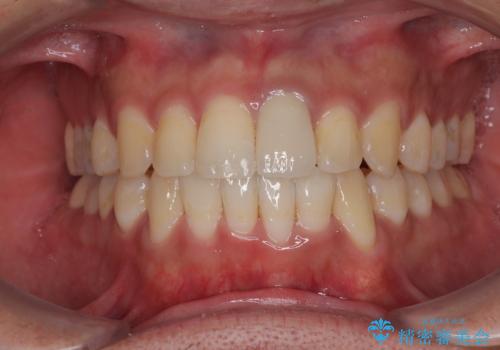

矯正治療後には気になっていた前歯をセラミッククラウンにし、自然な口元に仕上げることができました。